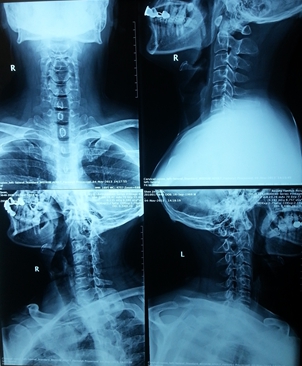

图1. 颈椎病术前